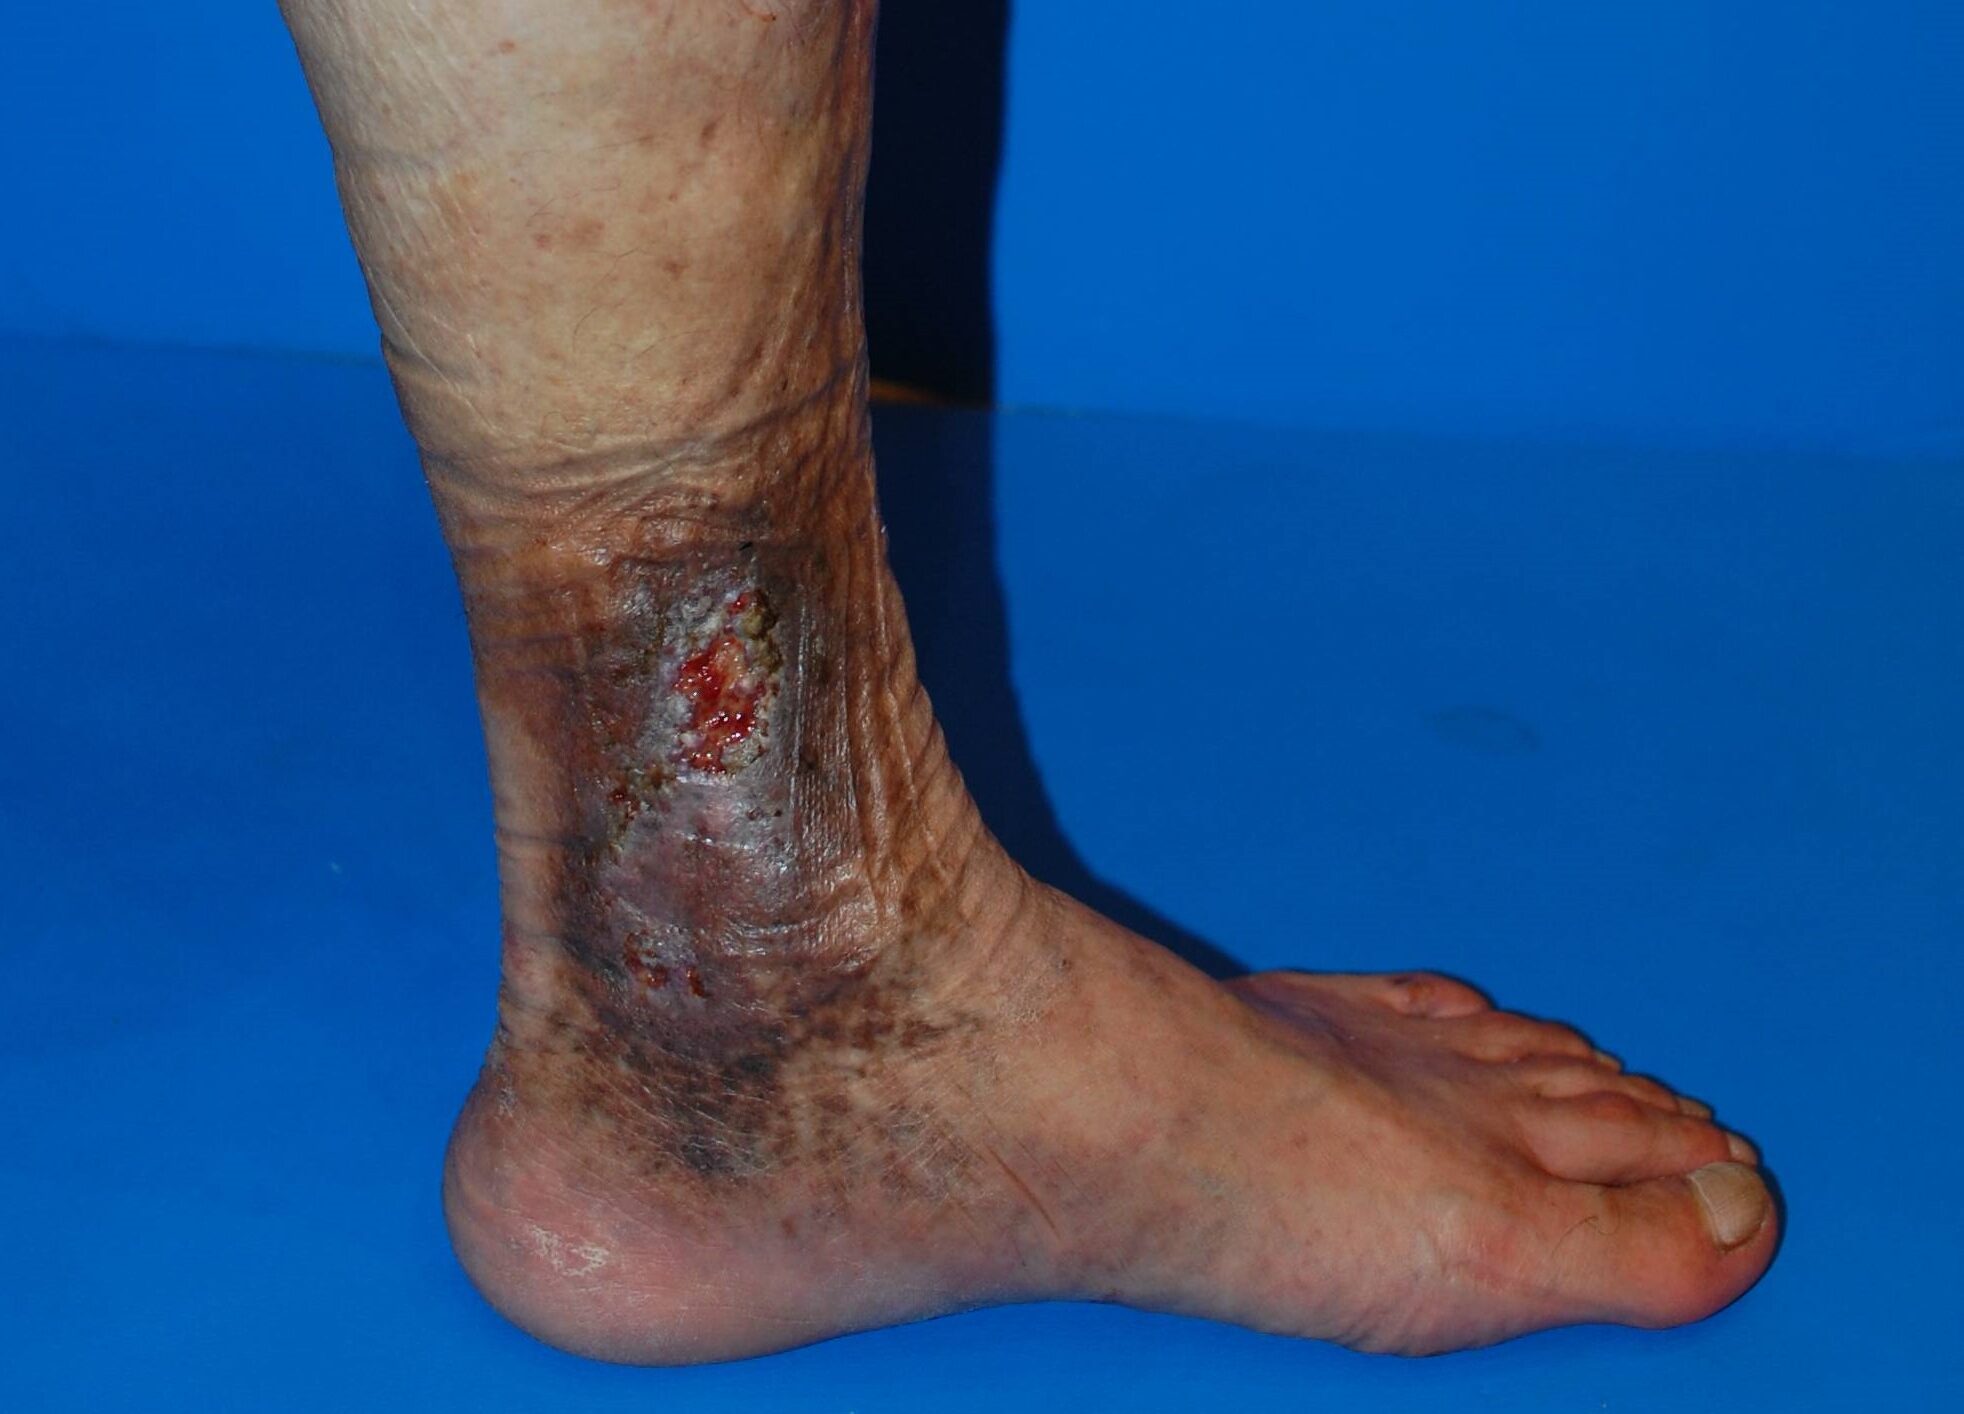

下肢静脈瘤による色素沈着は、足首〜ふくらはぎ内側に茶色〜黒っぽい変色が広がり、かゆみ・乾燥・皮膚の硬化を伴うのが典型です。前脛骨部よりも内果(内くるぶし)周囲が目立つケースが多く、光が当たるとテカり(光沢)が出ることもあります。

典型例:内くるぶし〜足首にかけての褐色変化。乾燥・痒みを伴うことが多い。

放置リスク:潰瘍化の前に

- 皮膚の硬化・肥厚・弾力低下

- 掻破によるびらん・出血・浸出液

- 静脈うっ滞性潰瘍(難治性)への進行

下肢静脈瘤による皮膚潰瘍

潰瘍化すると日常生活への影響が大きく、治癒にも時間がかかります。早期の超音波検査と適切な治療選択で進行を止めましょう。